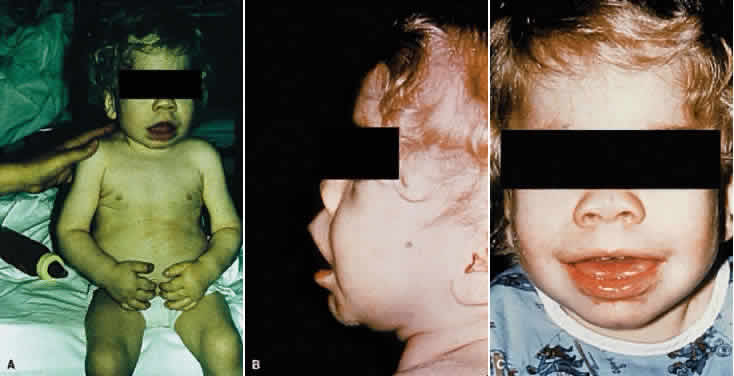

Manifestations develop in infancy and early childhood and become more apparent with increasing age. The head tends to be large and misshapen. Scaphocephaly due to premature closure of the sagittal suture is common; there is often a prominent longitudinal ridge along the sagittal suture. The facial features characteristically are coarse and the expression dull (Fig. 1). Hypertelorism is usual and the orbits are shallow; the eyes appear wide-set and prominent. The lids tend to be puffy, the brows prominent. The nose is broad, with wide nostrils and a flat bridge. The ears may be large and low-set. The lips usually are patulous; the tongue is large and protuberant. The teeth generally are small, stubby, and widely spaced; the gums are hyperplastic.

As mentioned in the description of the facies, the eyes tend to be wide-set and prominent owing to hypertelorism and shallow orbits, the lids tend to be puffy, and the brows are heavy and the lashes coarse. These features are seen to some degree in other mucopolysaccharidoses also.